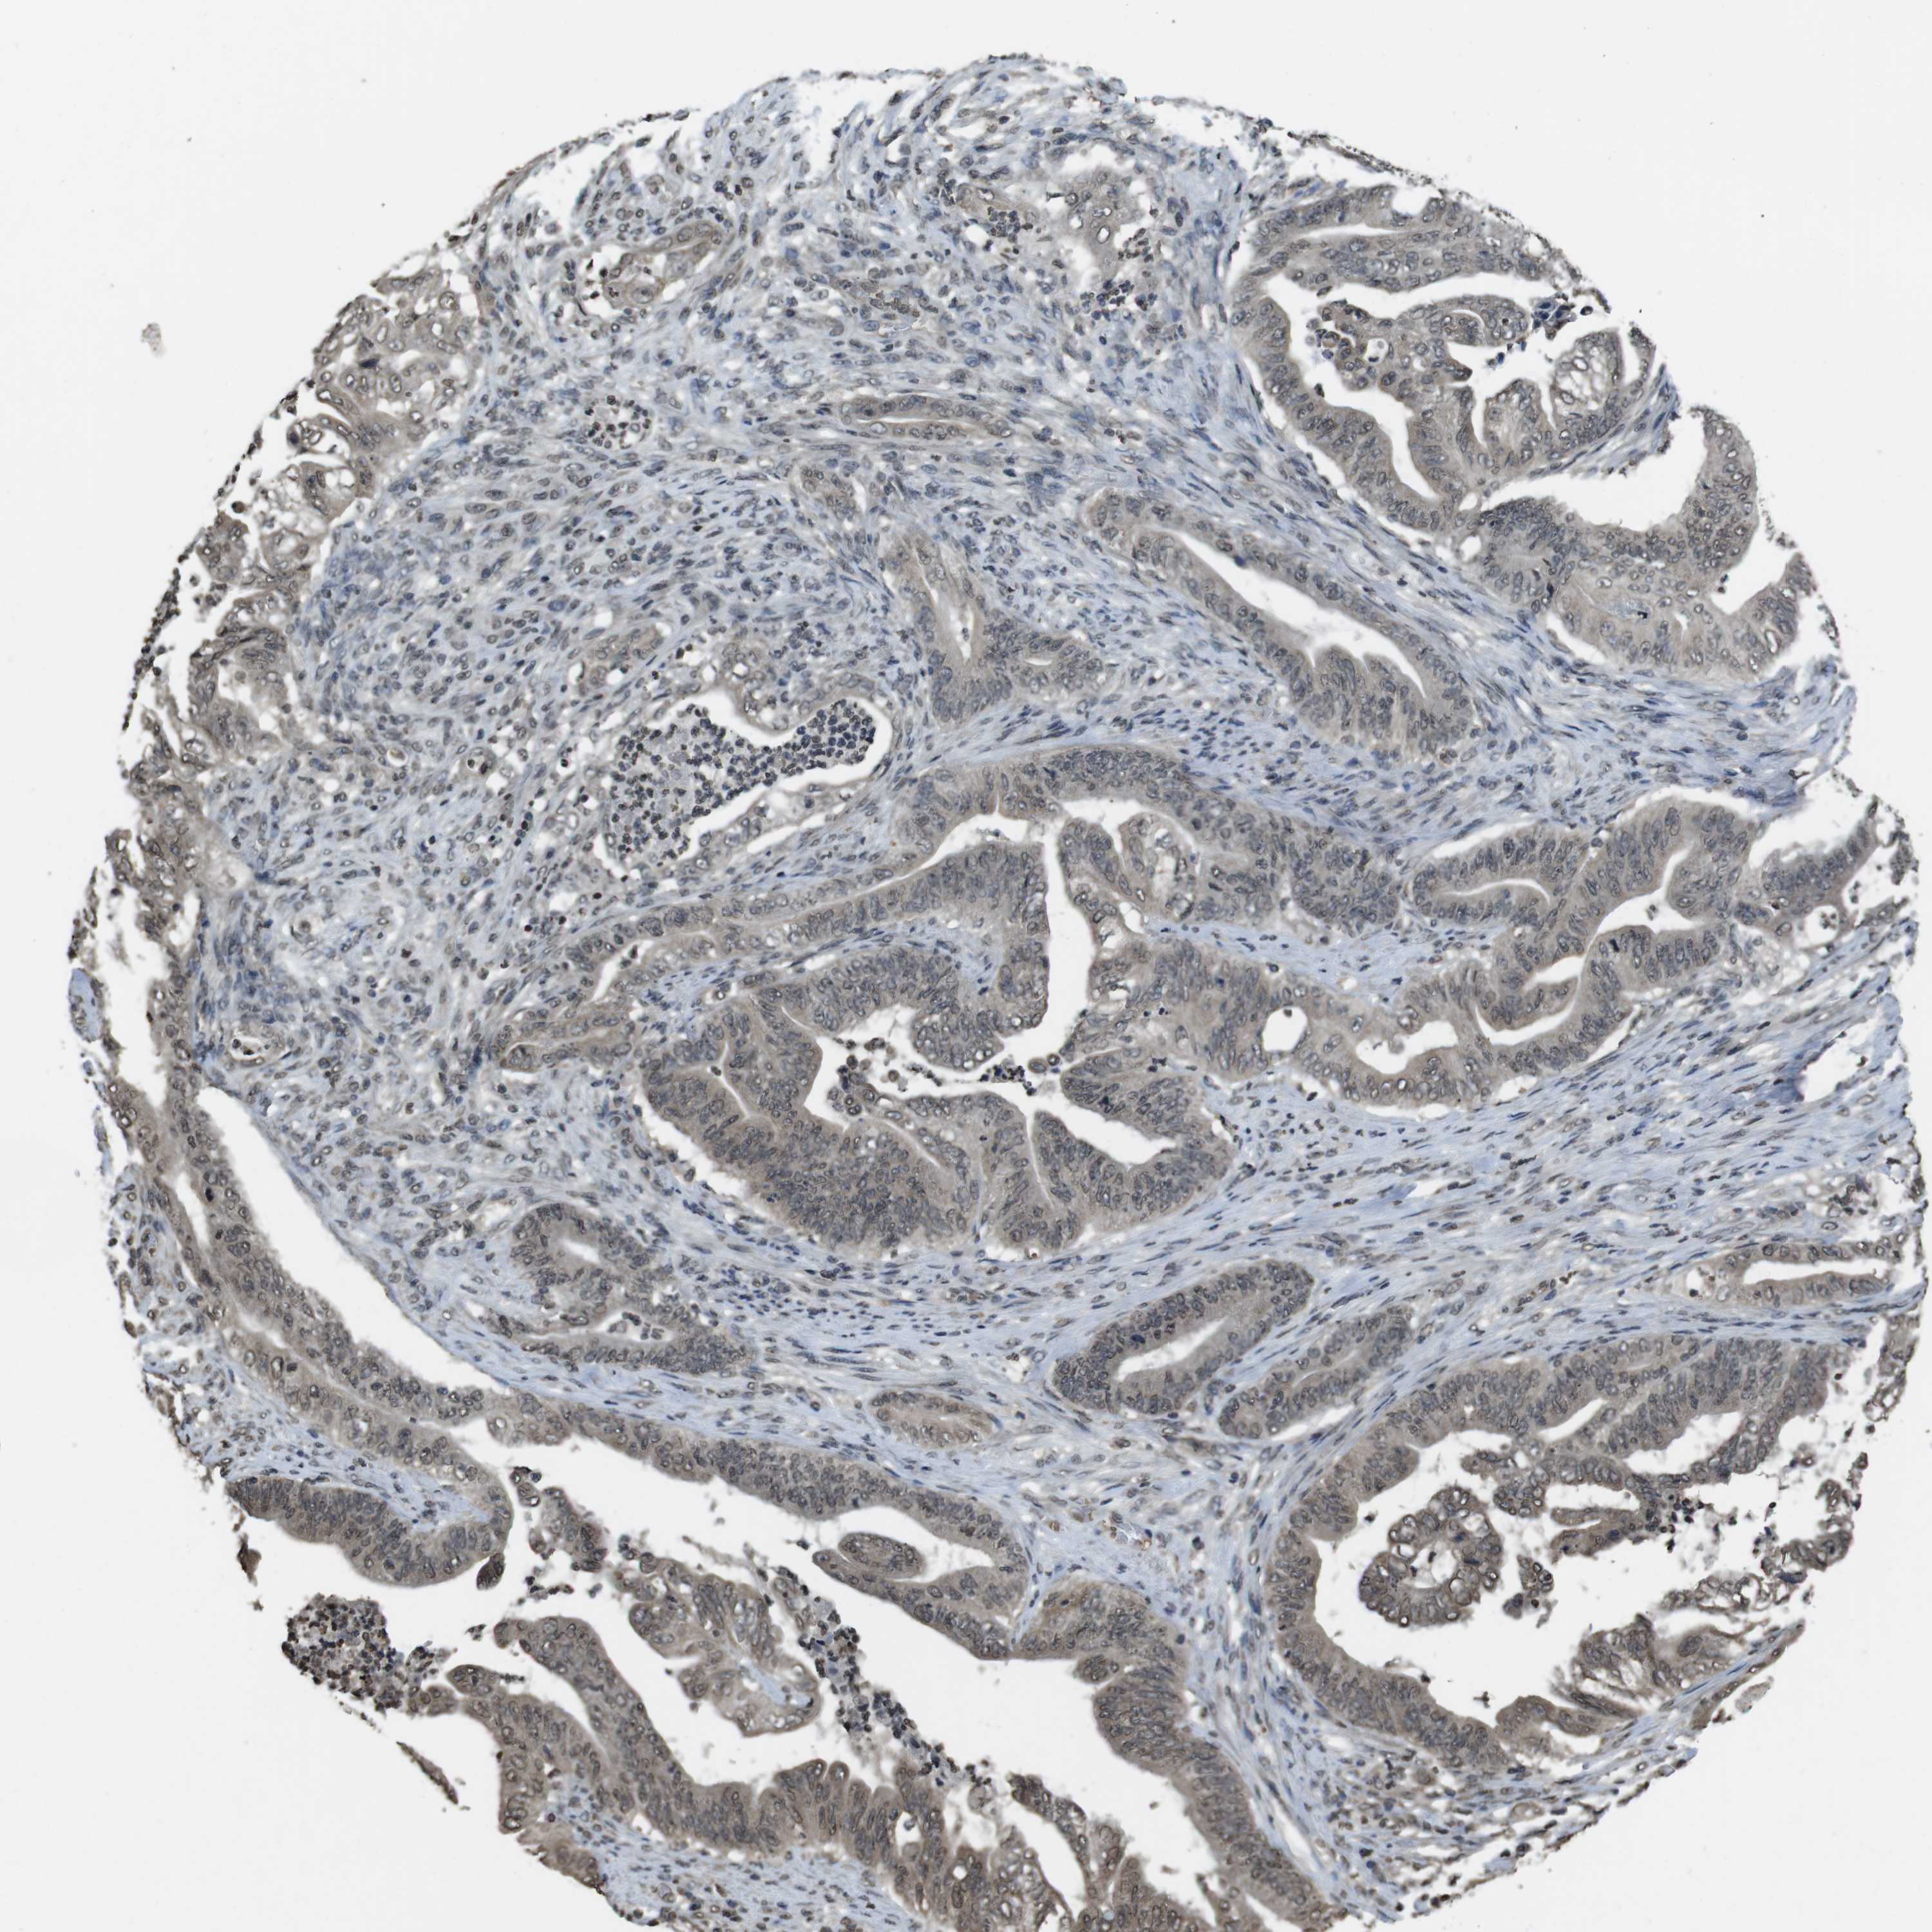

STOMACH CANCER - Protein expressioni

A mouse-over function shows sample information and annotation data. Click on an image to view it in a full screen mode. Samples can be filtered based on level of antibody staining by selecting one or several of the following categories: high, medium, low and not detected. The assay and annotation is described here.

Note that samples used for immunohistochemistry by the Human Protein Atlas do not correspond to samples in the TCGA dataset.

Antibody stainingi

Antibody staining in the annotated cell types in the current human tissue is reported as not detected, low, medium, or high, based on conventional immunohistochemistry profiling in selected tissues. This score is based on the combination of the staining intensity and fraction of stained cells.

Each image is clickable and will lead to virtual microscopy that enables deeper exploration of all samples and also displays staining intensity scores, fraction scores and subcellular localization as well as patient and tissue information for each sample.

Antibody HPA028289

Antibody CAB010296

Staining

High

Medium

Low

Not detected

Intensity

Strong

Moderate

Weak

Negative

Quantity

>75%

75%-25%

<25%

None

Location

Nuclear

Cytoplasmic/membranous

Cytoplasmic/membranous,nuclear

Adenocarcinoma, NOS

Adenocarcinoma, High grade